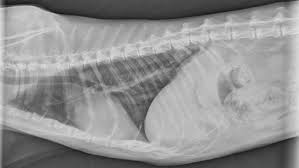

Lung Tumors Lap Of Love from www.lapoflove.com Lung cancer also is one of the toughest to beat. Lung cancer, also known as lung carcinoma, is a malignant lung tumor characterized by uncontrolled cell growth in tissues of the lung. Both types of lung cancer primarily affect cats that are over ten years of age. How long do outdoor cats live? Cats (pets) can have other cancer types that metastasize to the lungs. Answering the question, how long do cats live for, is not as simple as one might think! Lung cancer is a type of cancer that begins in the lungs. They explain why an indoor cat has a better chance of living longer than other cats.

Lung cancer is a type of cancer that begins in the lungs. Be aware that dogs with multiple lung masses may be the result of a fungal infection and not cancerous. Learn how quickly lung cancer grows, where it may spread in the body, and how long people can live with this condition. How long can cats live with rabies? Primary lung cancer, or tumors originating in the lung, are relatively uncommon in dogs (less than 1% of all cancers in dogs), although the number has been increasing. There are a lot of factors that determine survival witho. Finding lung cancer earlier and making new treatments available are helping more lung cancer survivors live longer. Lung cancer is the most common leading cause of death among elderly cats. Unfixed cats are at risk of developing testicular cancers, breast. How long can dogs live with cancer? Cancer survival is dependent on many factors, from the patients' underlying health conditions to how soon it is detected. Furthermore, how long can you live with cancer without knowing it? But other cancers can form and grow undetected for 10 years or more.